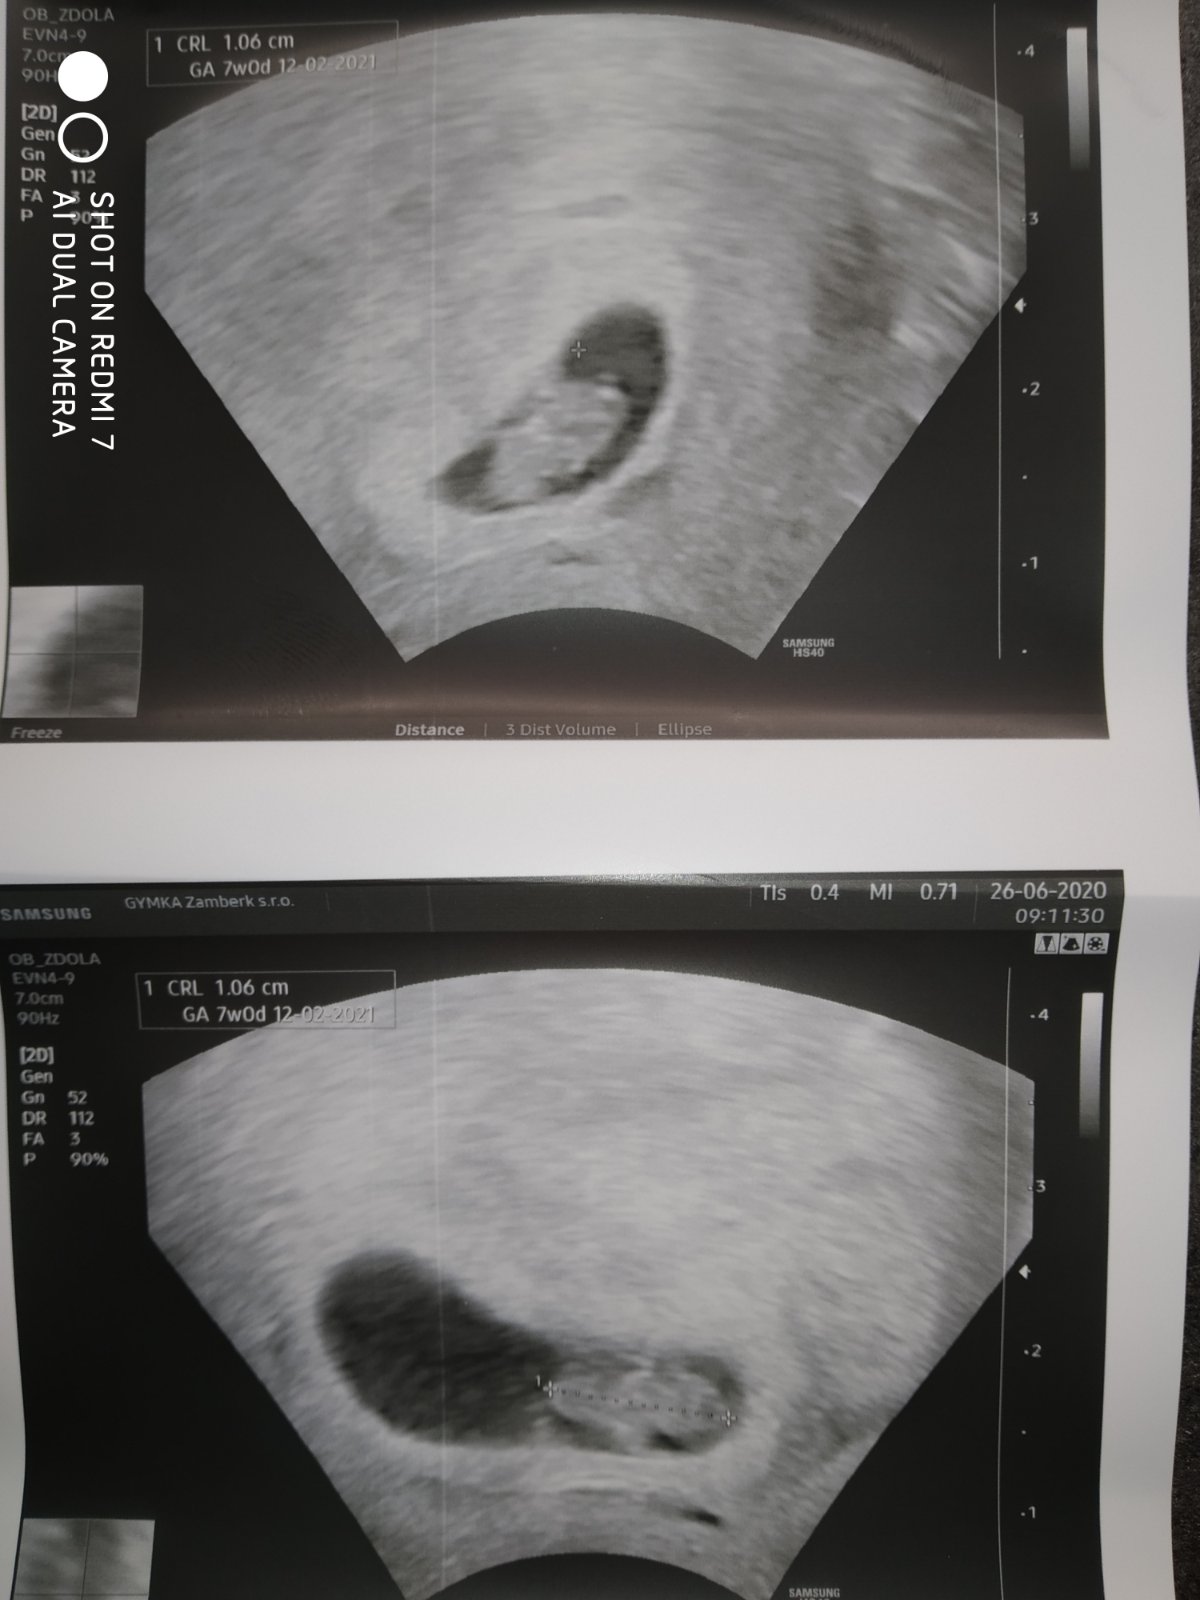

Tak teď jsem přišla od dr. Dle ms 5+6tt dle ultz 6+1tt žloutkový Vacek je vidět. Ale zatím neviděl srdeční akci.

@hanynka1704 no není vidět ❤️. Další kontrola 23.6.